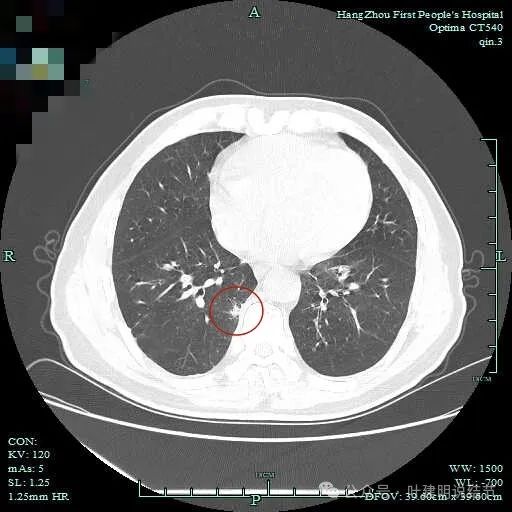

右下脊柱旁怎么也像有磨玻璃结节?但此处正常CT也是略显有慢性炎似的征象的,可这个病人明显结节状,还表面有细毛刺似的。

次病灶连续层面观察:

紧贴脊柱处混合密度,趴在脊柱上,这不像结节状。

但有小血管似的,磨玻璃部分界限较清。但此类异常影像在正常人的CT上也挺常见。

密度较高,确实像血管进入。但病灶片状,趴在脊柱上。

此层显得更呈小片状了。

与脊柱间似乎有间隙在,另见微小血管进入这条索状的偏高密度影处。